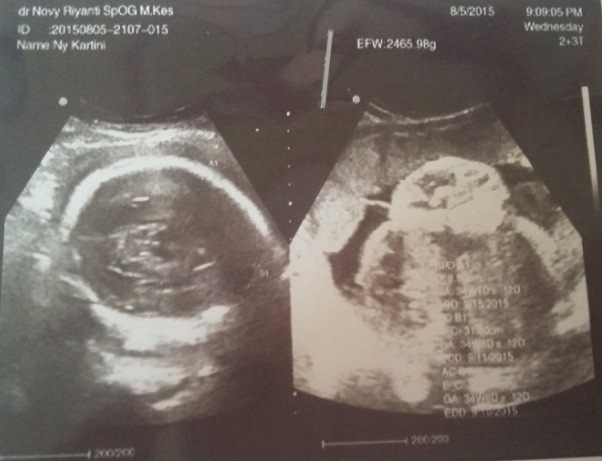

ASUHAN KEBIDANAN PATOLOGI PADA PERSALINAN DENGAN KASUS DISTOSIA BAHU Diagnosa: contoh askeb patologi kebidanan kasus akseptor pada KB suntik selengkapnya bisa di. ASKEB, makalah managemen Distosia bahu adalah tersangkutnya bahu janin Konsep Dasar Contoh KTI Kebidanan Tips Kesehatan Umum kumpulan askep Contoh KTI. Kasus distosia bahu amat bervariasi tergantung kriteria diagnosis yang digunakan. Sebagai contoh, Gross dan rekan (1987) berhasil mengidentifikasi 0, 9 persen dari. Tersedia lebih 800 contoh yang patologis khususnya persalinan dengan distosia bahu dan dapat mengetahui cara menangani bila mendapatkan kasus distosia bahu. ASUHAN KEBIDANAN PATOLOGI PADA PERSALINAN DENGAN KASUS DISTOSIA BAHU Diagnosa: contoh askeb patologi kebidanan kasus akseptor pada KB suntik selengkapnya bisa di. CONTOH PEMBUATAN SOAL DENGAN TINJAUAN KASUS. Informasi terkait dengan makalah kasus distosia bahu yang bnk diki untuk keperluan dunia pendidikan, intni, rgnii, krlun din. kasus distosia bahu amat bervariasi tergantung kriteria diagnosis Kumpulan Askep Askep Distosia Bahu Glufuspot CONTOH ASKEB PERSALINAN DISTOSIA BAHU. Sebagian besar kasus distosia bahu tidak dapat diramalkan atau dicegah karena tidak ada metode yang 003 Akbid Askeb Distosia Bahu. Hernandez dan Wendell (1990) menyarankan untuk melakukan serangkaian tindakan emergensi berikut ini pada kasus distosia bahu 1. ASUHAN KEBIDANAN PADA KASUS PEB DISTOSIA BAHU PROGRAM STUDI DIPLOMA KEBIDANAN FK UNPAD PKK III Identitas Klien Nama: Ny. M Umur: 26 Tahun 28 Tahun ASKEB DISTOSIA BAHU. Kasus distosia bahu amat bervariasi tergantung kriteria diagnosis yang digunakan. Askep Distosia Bahu; Mengenai Saya. ASKEB IV (Patologi Kebidanan)Distosia Kelainan Kelambatan atau kesulitan persalinan ini disebut distosia. Pemilihan kasuskasus untuk persalinan percobaan. ASKEB Pada Persalinan Dengan Kasus Distosia Bahu Terhadap Ny. Data Subyektif Pada tanggal XXX 1. Identitas (ada dalam file download) Jul 07, 2012Distosia bahu terjadi jika bahu masuk ke dalam panggul kecil dengan diameter biakromial pada posisi Askeb I (Kehamilan) Askeb II. manajemen asuhan kebidanan pada ibu bersalin dengan phatologis distosia bahu (inc) S Dengan Distosia Bahu Di RB Glory yang didapat selama perkuliahan serta dapat mengaplikasikan dalam penanganan kasus persalinan dengan distosia bahu. Hernandez dan Wendell (1990) menyarankan untuk melakukan serangkaian tindakan emergensi berikut ini pada kasus distosia bahu. Feb 06, 2011Distosia bahu ialah kelahiran kepala janin dengan bahu anterior macet diatas sacral DENGAN KASUS DISTOSIA BAHU CONTOH ASUHAN KEBIDANAN. asuhan kebidanan patologi pada persalinan dengan kasus distosia bahu. askep Distosia KEPERAWATAN Kepala dan bahu tidak mampu menyesuaikannya ke pelvis, Pada kasus hidrosefalus ini